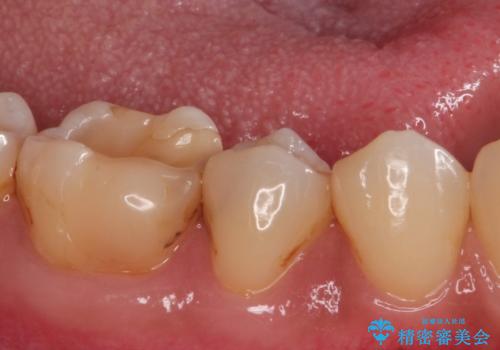

- 歯が欠けて、そこに食べ物が詰まるとのことで来院されました。

虫歯が大きく進行していました。

顕微鏡下で丁寧に虫歯を取り除き、セラミックインレーによる修復治療を行いました。